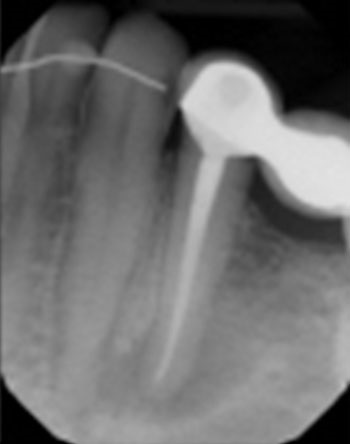

This patient was very worried that she was going to lose her front tooth, #8. Her dentist was concerned that the root had been split by a large, tapered post given the context of the bilateral radiolucencies located at the bottom of the post.

No crack was seen when the post was removed, nor were any lateral canals located. This tooth was treated in three visits over six months using a calcium hydroxide intracanal medicament. It is possible that a nidus of bacteria remained in the gap between the obturation and the post.

The patient’s symptoms resolved after the first visit. The case was obturated after confirming full bony healing. She is still extremely appreciative of the efforts made to save her front tooth.

Fig. 19: Preop PA.